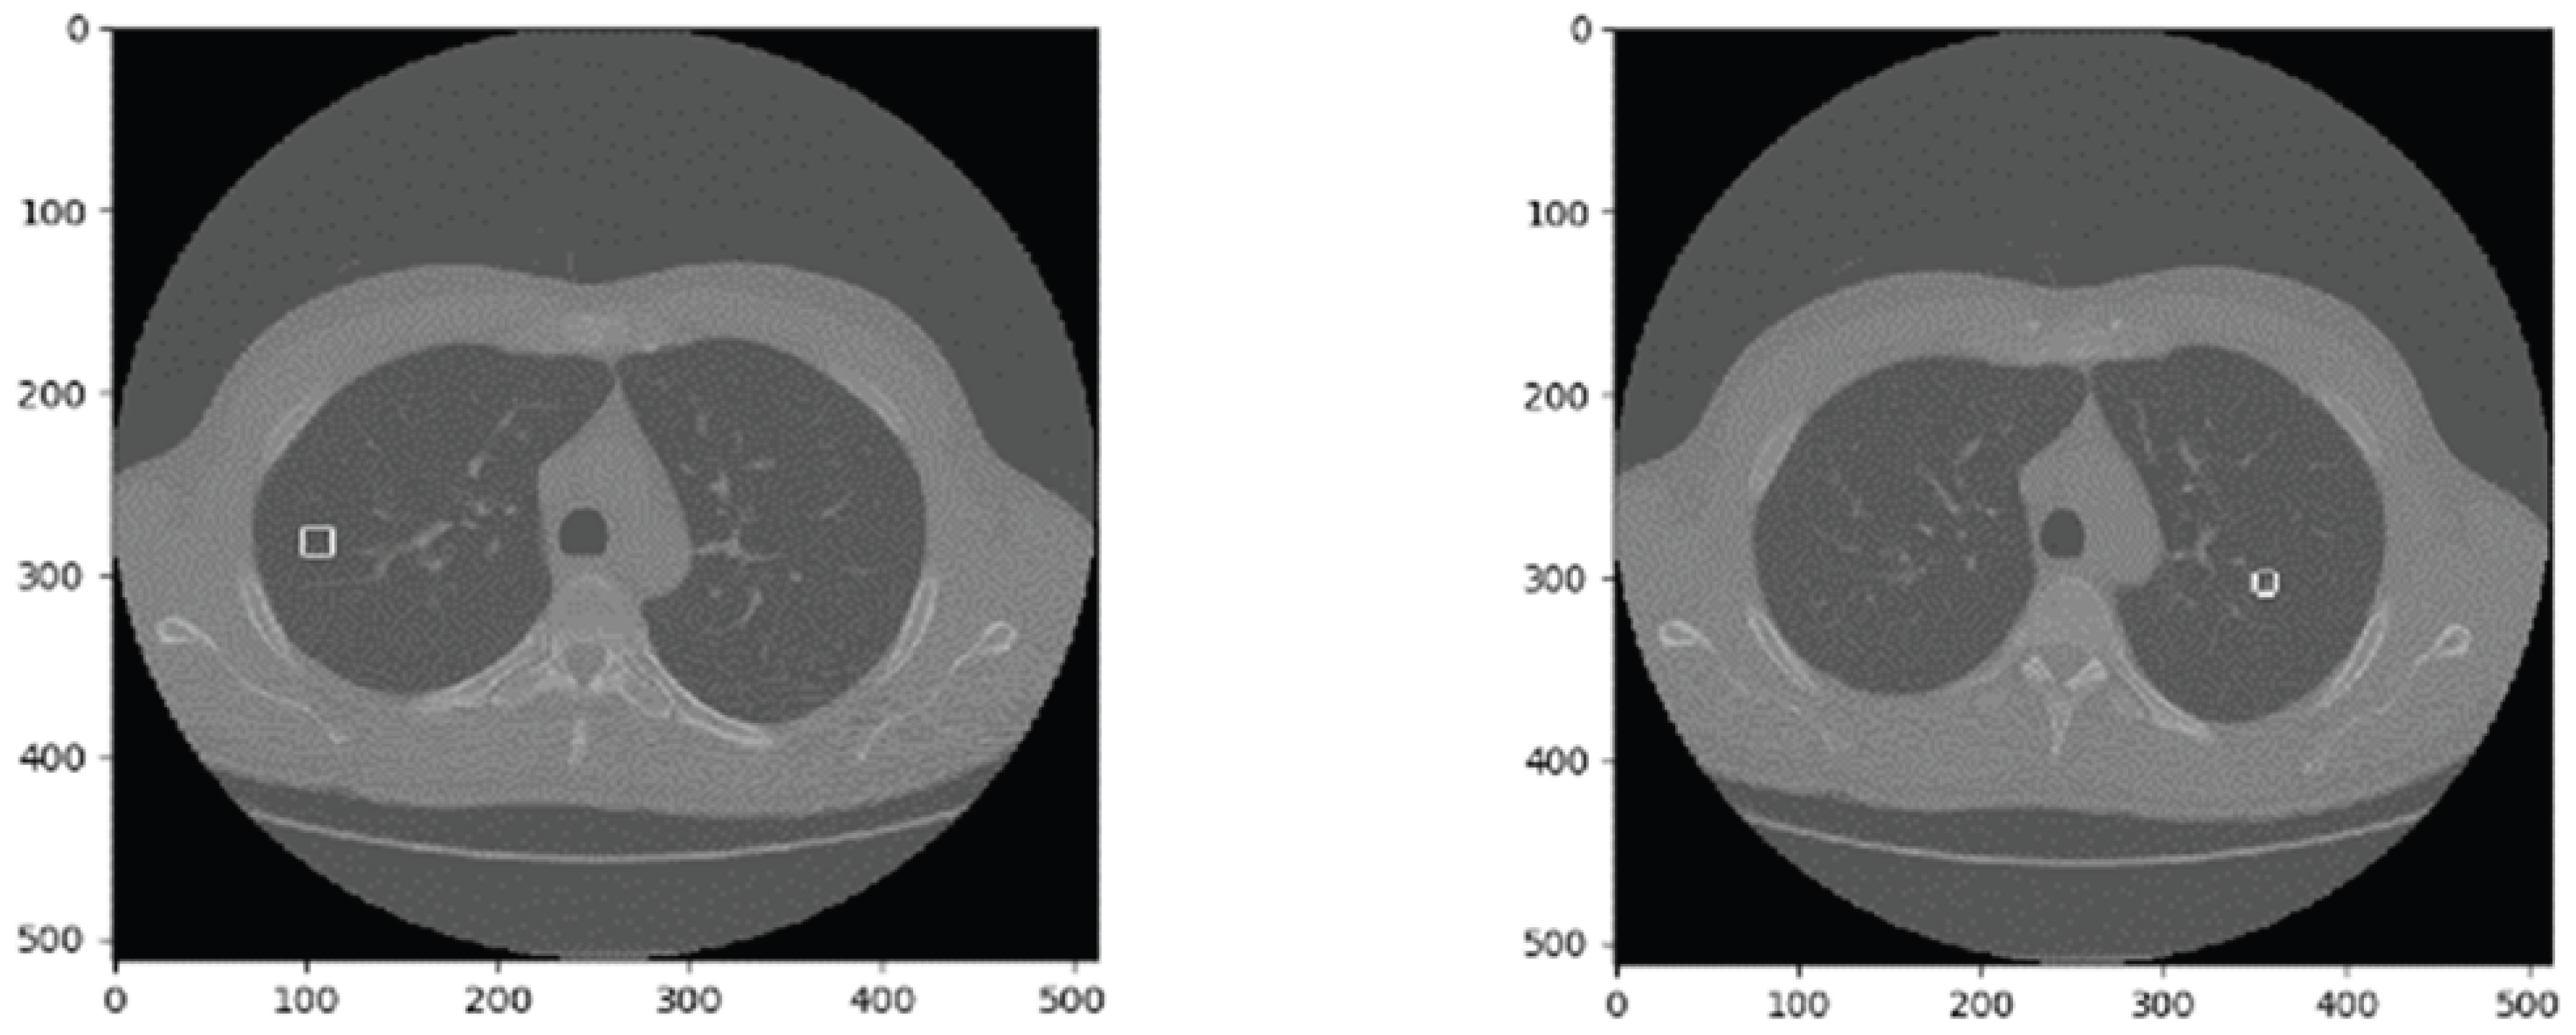

This paper uses the LUNA16 dataset. As a publicly available lung nodule dataset and a subset of LIDC-IDRI [34], LUNA16 includes CT images from 888 patients, divided into 10 subsets for storage. Each image set consists of mhd and raw files, where the mhd file provides basic image information, and the raw file stores pixel data. An example CT image is shown in Figure 1.

Figure 1. LUNA16 image examples.